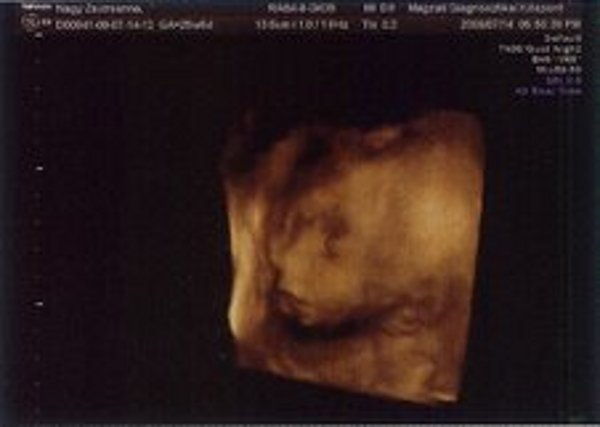

Kistörpe! Tényleg nagyon rohan az idő. Gratula Nektek! Majd hozz képet az uh-ról!